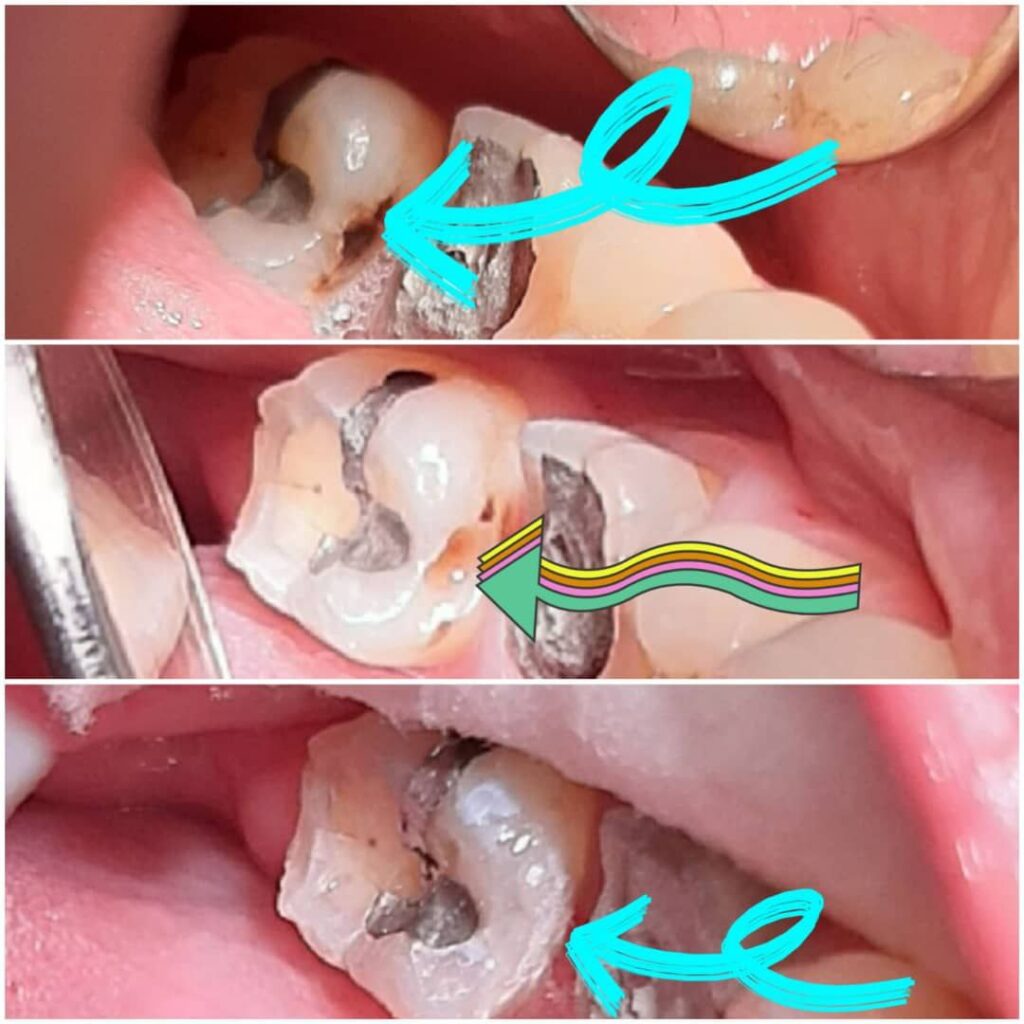

چگونه بهترین گزینه ترمیمی را برای درمان دندانهای آسیبدیده انتخاب کنیم؟

این مهم به بهترین شکل توسط یک دندانپزشک مجرب و خوب مشخص میشود. دندانپزشک با بررسی دندانها و موقعیتی که دارند و همچنین وضعیت دندانهای سالم باقیمانده بهترین شیوه درمانی را توصیه خواهند کرد.